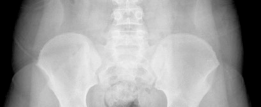

Comprehensive radiographic evaluation is mandatory. Standard imaging includes an anteroposterior view of the pelvis and a cross table lateral view of the affected hip. The frog leg lateral view is strictly contraindicated in unstable slips due to the risk of exacerbating the displacement and causing iatrogenic vascular injury.